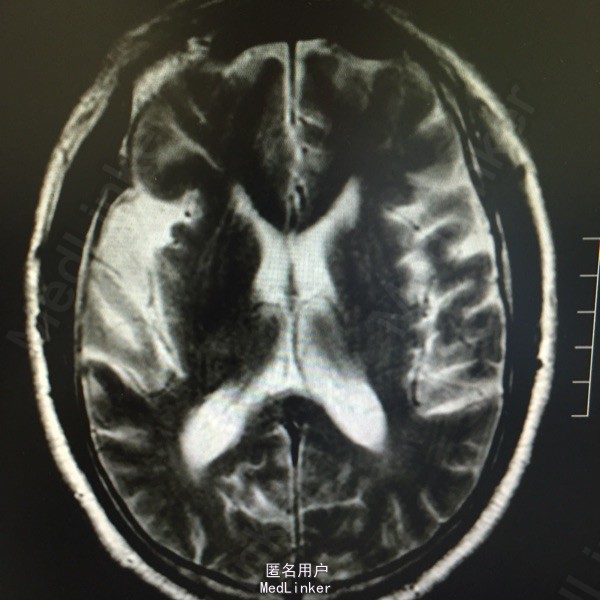

头痛伴视物双影5天。既往高血压、糖尿病、脑梗死。该患于入院前5日无明显诱因出现视物双影,偶伴头痛,不伴有恶心、呕吐,无视物旋转,无吞咽困难,病程中无肢体活动障碍,无言语不清,无意识障碍及尿便失禁。曾有中耳炎病史,伴有听力减退,曾于入院前3日在眼科医院激光治疗眼底出血。为求进一步诊治而来我院。

查体:神清语利,左眼内收受限,鼻唇沟对称,伸舌居中,双耳听力减退,肌力肌张力正常,双下肢病理症(-)颈强(-)。

诊断:脑梗死、高血压、2型糖尿病、高脂血症、中耳炎 治疗:营养神经、改善循环、神经生长因子、降脂、抗炎对症治疗。